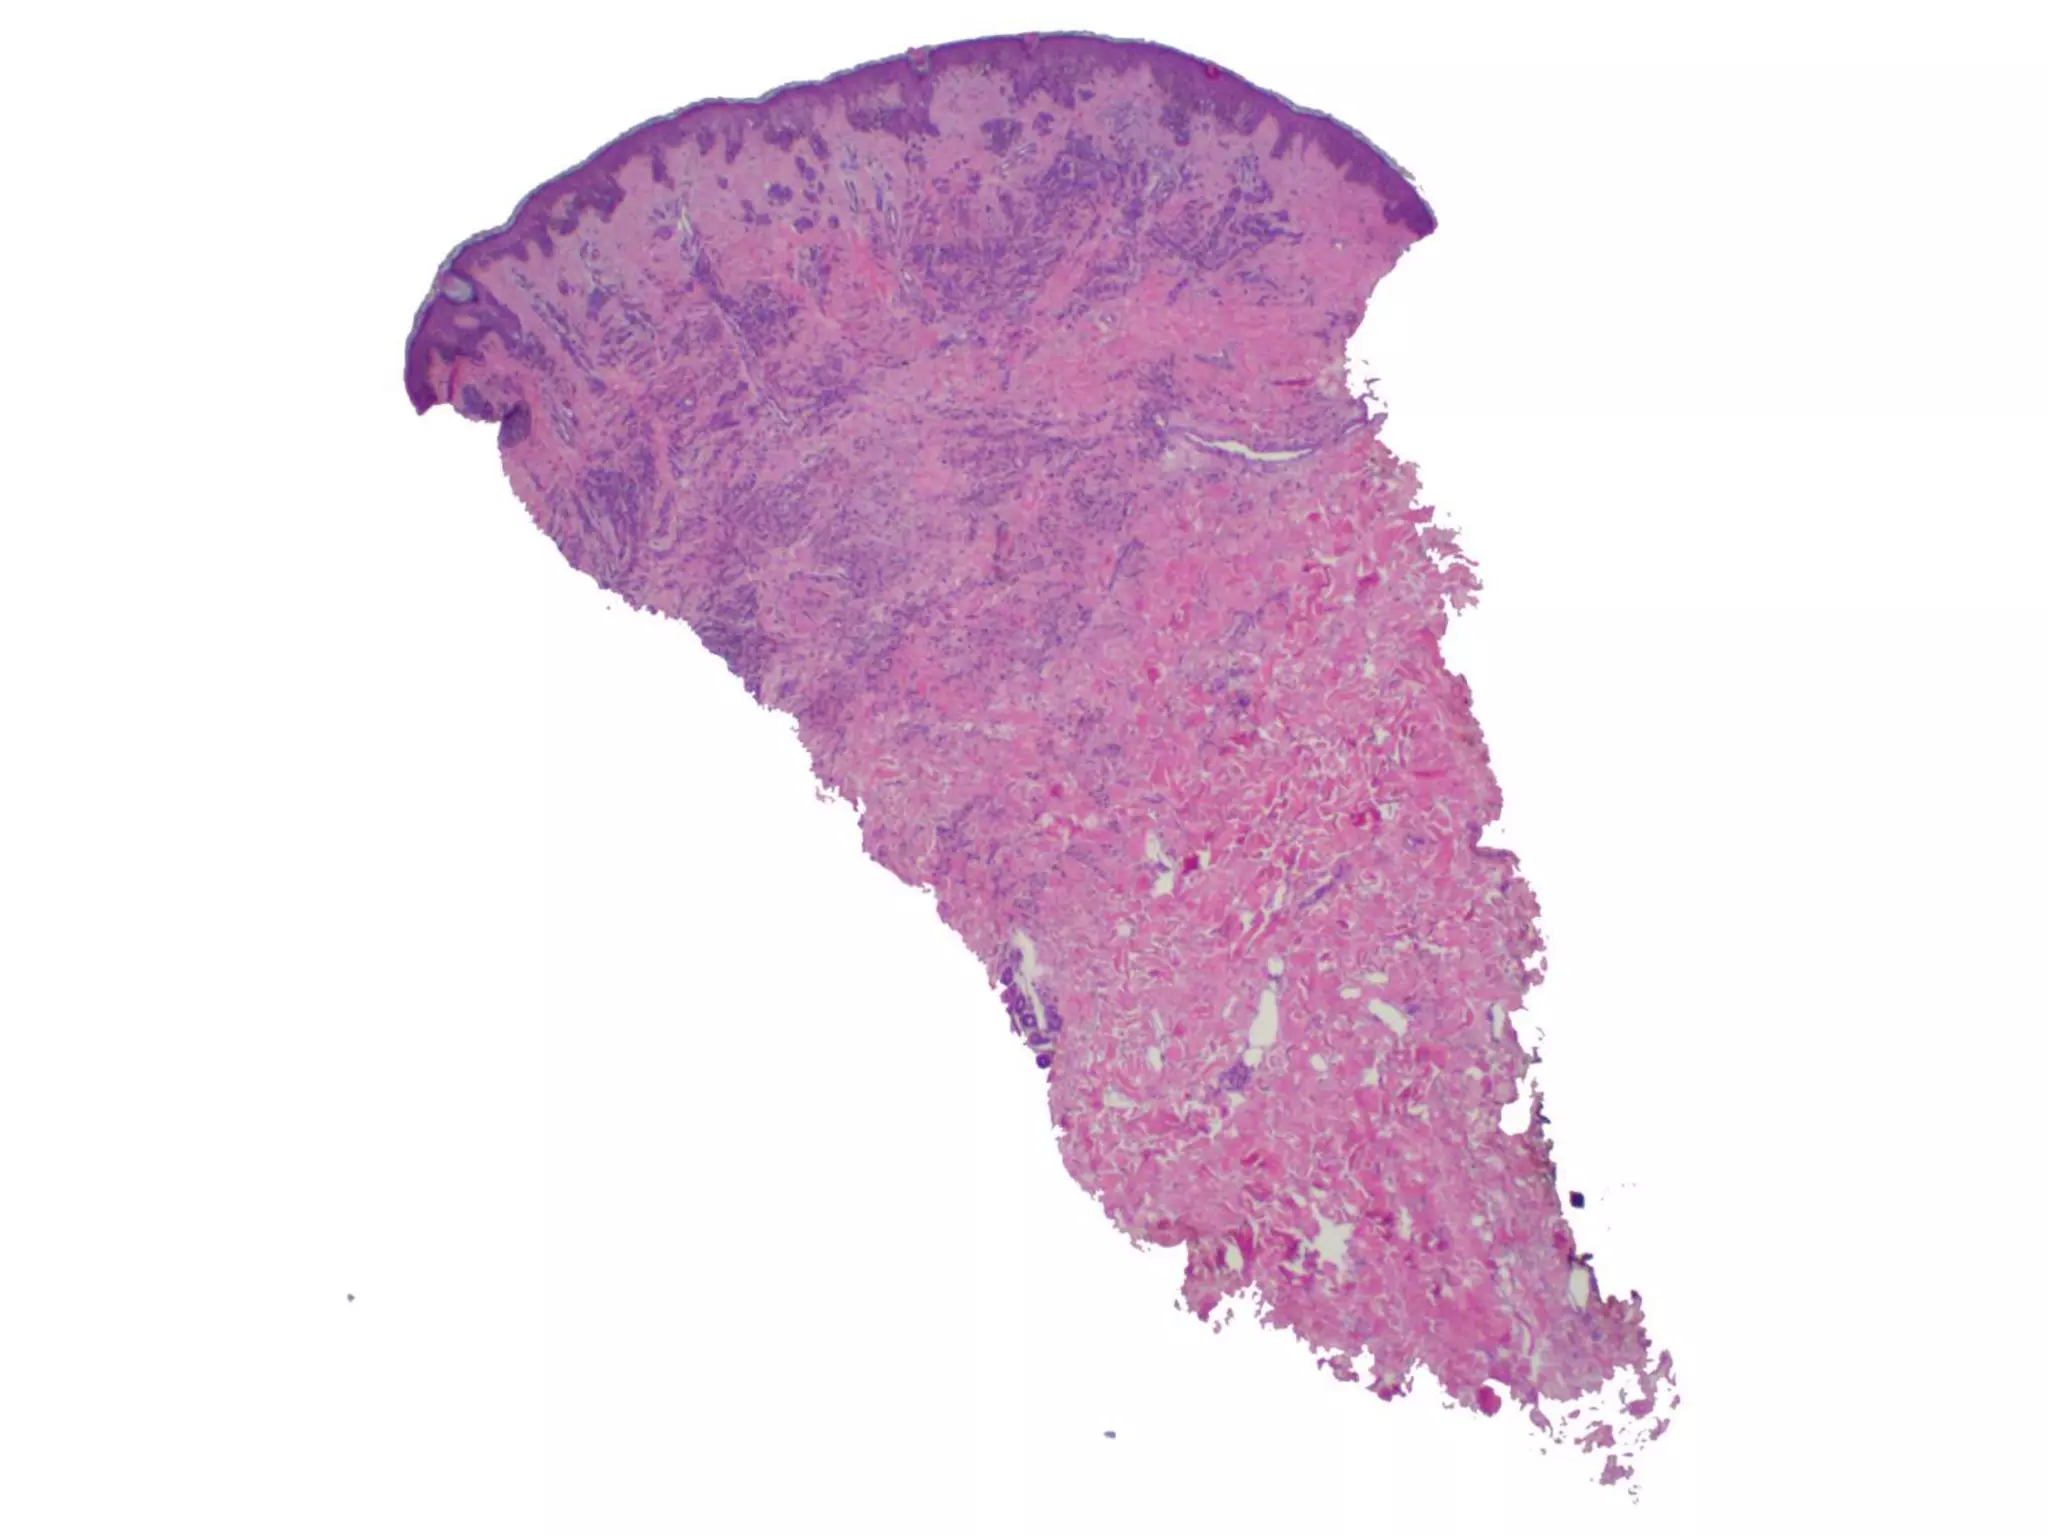

The document provides an overview of dermatopathology, including methods and techniques for skin biopsies such as shave, punch, and ellipse methods. It discusses key terms associated with dermatopathology, such as acantholysis and granulation tissue. Additionally, it references presentations by professionals in the field and essential dermatology resources.